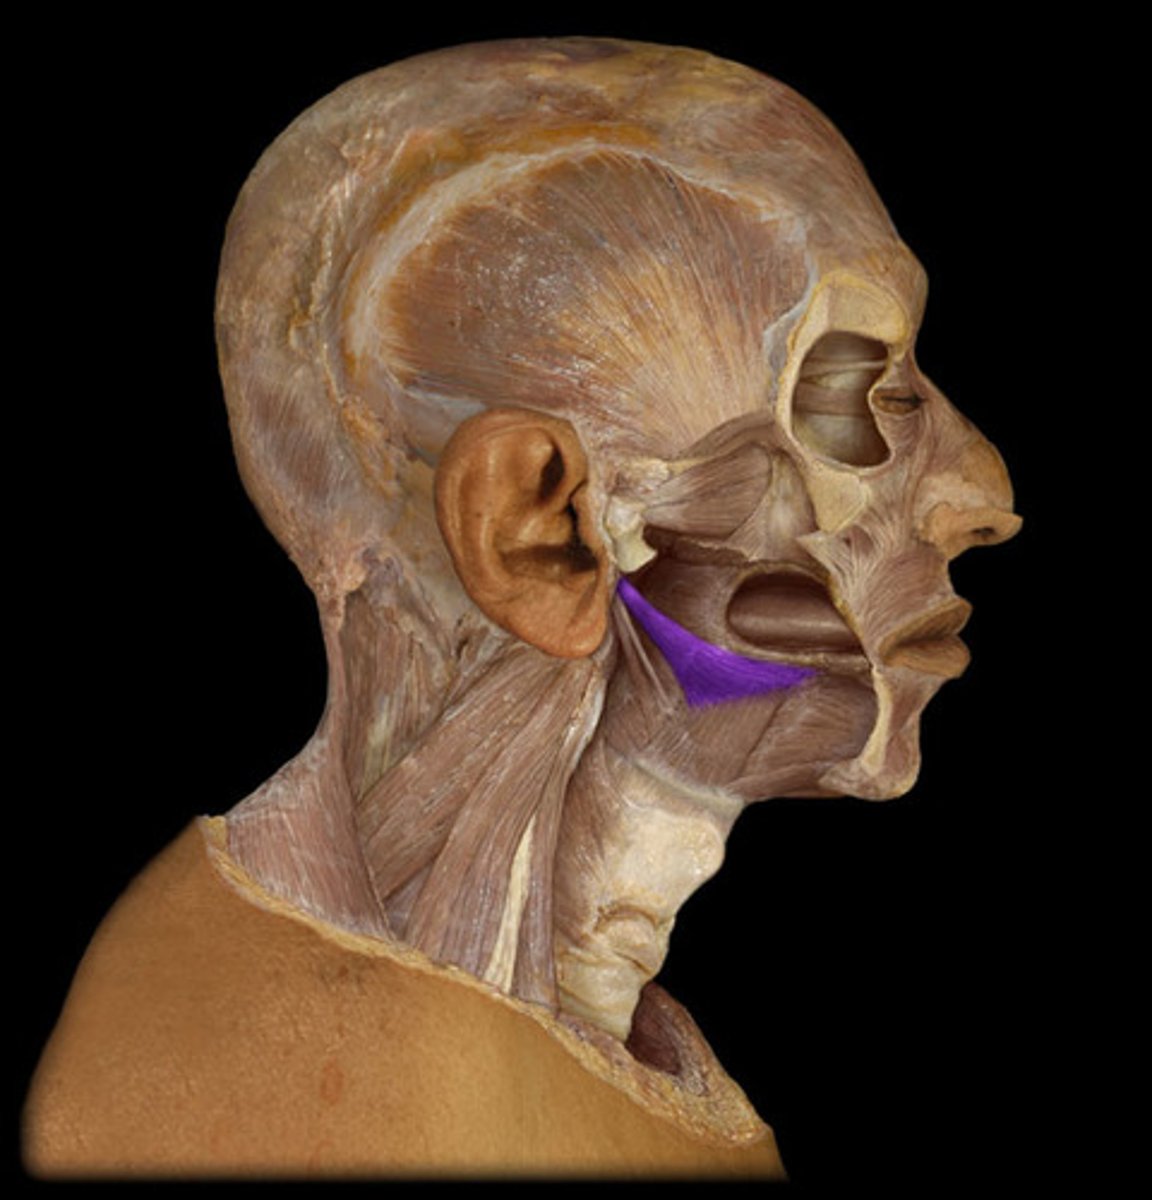

New cards